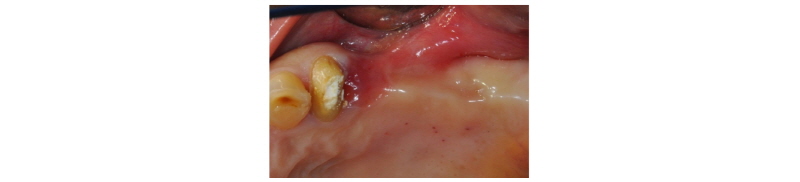

57세의 여성 환자로 기존 브릿지 보철 수복물(#24-27)의 상악 좌측 제 2대구치의 심한 우식으로 인해 내원하여 해당 치아를 발거하였다(Fig. 1). 상악 좌측 제 1 소구치는 근관치료를 시행한 후 보철 수복하기로 하였고 기존 pontic 부위였던 좌측 제 2 소구치와 발거된 제 2 대구치 부위에 #25i, #27i 2개의 임플란트 식립을 통한 브릿지 보철 수복물을 계획하였다(Fig. 2). 기존 pontic으로 유지되었던 좌측 제 2 소구치 부위는 치조제의 심한 수평적 치조골 흡수를 구강 내 임상검사를 통해 확인할 수 있었다. 전층 판막 형성후 상악 좌측 제 2 소구치 부위의 치조정 폭경은 약 2 mm 정도로 측정되었다(Fig. 3, 4). 치조골의 구개측에 약 1 mm의 치조골이 남도록 high speed carbide round bur를 이용하여 치조정에 horizontal intraosseous groove를 형성하였고 협측골의 근심, 원심측에 2개의 vertical intraosseous groove를 형성하였다(Fig. 5). Chisel과 ridge spreader drill (RS kit, Dentium, Korea)을 이용하여 점차적으로 협측 골판을 구개측으로부터 분리시켰다(Fig. 6). Osteotome을 이용, 식립 깊이까지 적용하여 임플란트 식립 부위를 형성하였고 Ø4.3 × 10 mm (Implantium, Dentium, Korea) 임플란트를 식립하였다(Fig. 7). 발치 후 치유된 상악 좌측 제 2 대구치 부위는 상악동 거상술(수직 접근법)을 시행, 골이식을 한 후 4.8 × 10 mm (Implantium, Dentium, Korea)를 식립하였다(Fig. 8). 이후 이종골 이식재(Bio-Oss®, Geistlich, Switzerland)를 식립된 임플란트와 협,구개 측 치조골판 사이의 gap과 협측골판 상방에 적용하고 흡수성 교원질 차폐막(Bio-Gide®, Geistlich, Switzerland)로 피개한 다음 감장절개를 통해 장력없이 봉합하였다(Fig. 9-11). 이후 구강 내 검사 및 방사선 검사를 통해 수술부위 치유상태를 확인하였고 특이한 임상적 소견없이 정상적으로 잘 치유되었다(Fig. 12). 약 3개월 10일 정도의 치유기간 후 이차수술을 시행하였다(Fig. 13). 판막 거상 후 치조제 분할술을 시행하였던 상악 좌측 제 2 소구치 부위에 잘 형성된 신생 골양조직이 관찰되었다(Fig. 14). 상악 좌측 제 2 소구치 부위와 상악 좌측 제 2 구치 부위에 치유지대주를 장착하였고 상악 좌측 제 1 대구치 부위에 추가적으로 임플란트를 1회법으로 식립하였다(Fig. 15). 이차수술 이후 정상적으로 치유가 진행되어 약 2개월 후 최종 보철물 수복을 하였다(Fig. 16, 17). 약 1년 정도의 follow-up시 구강 내 검사와 방사선 검사를 통해서 임플란트 주위 연조직과 변연골이 잘 유지되고 있음을 확인하였다(Fig. 18).

Fig. 3. Clinical view. Pre-op. |